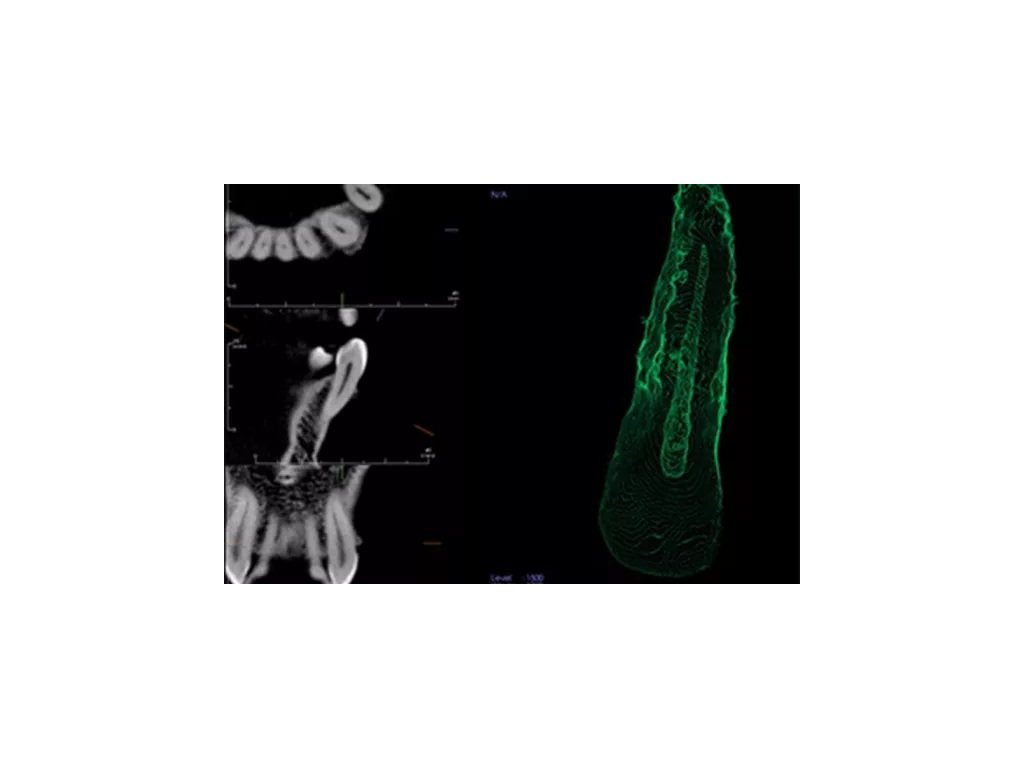

Endo zobrazení nabízí komplexnější zobrazení vnější i vnitřní struktury, tedy i vizualizaci pulpy nebo přímá vizualizace kořenového kanálku. Můžete si tedy jednodušeji zobrazit vnitřní morfologii kanálku, včetně zakřivení kořenů, jejich počet a lokalizaci vstupů kořenových kanálků. V endodontické vizualizaci můžete také provádět přesná měření.